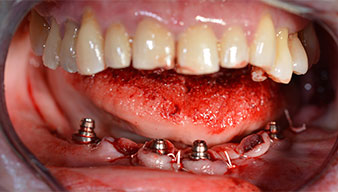

Un CT Scan à faisceaux coniques tridimensionnel (CBCT, Planmeca) a été réalisé au préalable afin de réduire les risques. Il a révélé une qualité et une quantité d'os disponible suffisante pour l'intervention chirurgicale et la restauration immédiate par la méthode All-on-four. En suivant le protocole de ce concept, les implants sont insérés au niveau de 35, 32, 42 et 45 en inclinant les implants distaux jusqu'à 45°, le profil d'émergence se déplace ainsi vers l'arrière et produit un polygone de stabilisation plus large (Fig. 3).

Le prochain réglage programmé est destiné à la mise en place des implants. Dans notre cabinet, nous appliquons généralement un couple de 32 Ncm pour cette phase (Fig. 12 et 13).

Une grande stabilité primaire est une exigence essentielle à la restauration immédiate. Pour s'en assurer, le forage n'a pas été taraudé ici. L'unit de chirurgie Implantmed W&H utilisé ici est doté d'un mode spécial adapté qui peut être directement sélectionné et est indispensable à de nombreuses indications. Lors du positionnement des implants, les derniers tours ont été effectués avec une valeur supérieure à 32 Ncm et ont été effectués à la clef à cliquet. Dans un tel cas, nous recommandons d'utiliser la fonction d'auto -taraudage de l'implant et de tourner plusieurs fois les implants vers l'arrière et vers l'avant.

Ceci permet à l'implant de s'approcher de la position finale progressivement sans exercer de pression excessive sur l'os (Fig. 14).

Les piliers angulés (35°) ont été vissés pour compenser la divergence des implants distaux. Ainsi, le profil

d'émergence de tous les implants doit être le plus perpendiculaire possible par rapport au plan occlusal. Il s'agit

d'une condition préalable à la pose en occlusion de la prothèse provisoire puis permanente (Fig. 15 et 16).